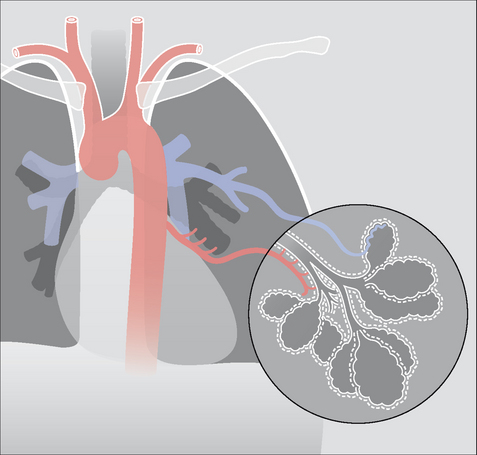

The lung has two distinctive and separate blood supplies (Fig. 30.1):

image Low pressure pulmonary arteries which end in a network of capillaries supplying the alveoli only.

image High pressure bronchial arteries arising from the aorta. Their sites of origin can vary—usually from the proximal descending aorta. Typically, two bronchial arteries supply the left lung and a single bronchial artery supplies the right lung. These arteries feed the bronchial walls up to and including the terminal bronchioles. They also supply the connective tissue of the lung as well as the visceral pleural membrane.

Figure 30.1 The two separate blood supplies to the lungs. The bronchial arteries (high pressure) arise from the aorta. The pulmonary arteries (low pressure) arise from the right side of the heart.